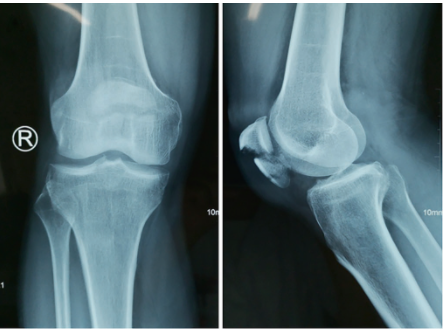

图2. 18岁男性患者因跌倒导致右侧IPFP。

A术前右膝关节正侧位x线片。

B撕脱骨折复位后,使用克氏针固定骨折块,使用1号可吸收缝线进行缝线固定。

C术后无张力外固定装置。

D术后右膝关节正侧位x线片。

E术后外架情况。

F外固定架拆除后膝关节功能良好。

G外固定架拆除后右膝关节正侧位x线片。